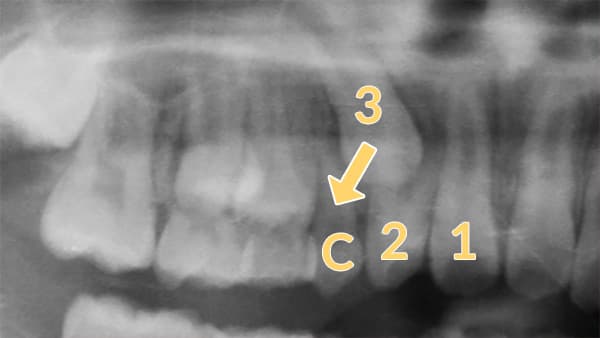

まだ生えていない永久歯が、変な位置に生えてきてしまうことはよくあります。(レントゲンを撮らないとわからない問題点です)変な方向に生えそうな永久歯は、乳歯をタイミングよく抜歯することで、良い位置に誘導することができる場合があります。

左図の場合、3番(犬歯)が、2番の歯根方向に生えています。このままだと2番の歯根にぶつかってしまったり、八重歯になって生えてきたりすることもあります。

乳犬歯(C)を早めに抜歯することで、正常な位置に生えてくるよう誘導します。